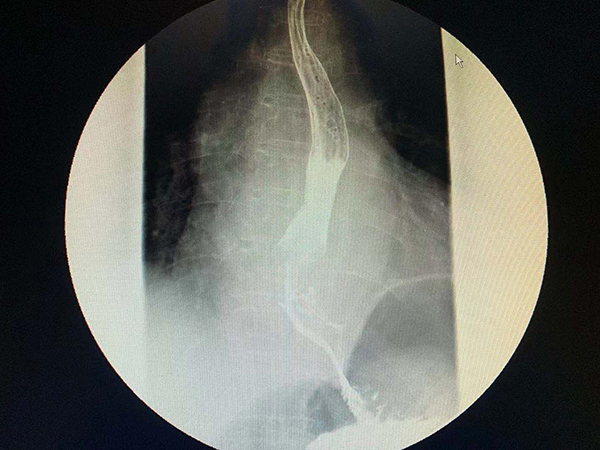

黃淮網(wǎng)  近日,一例81歲老人因進(jìn)食困難在地方醫(yī)院檢查發(fā)現(xiàn)為食管癌,同時(shí)還發(fā)現(xiàn)肺上還有一病灶,性質(zhì)不能確定,因病情復(fù)雜慕名來到徐醫(yī)附院就診。

徐醫(yī)附院胸心外科主任王國祥接診后,仔細(xì)分析發(fā)現(xiàn)肺部病灶也是肺癌,同樣需要切除。患者家屬積極要求同期手術(shù)根治肺和食管兩個(gè)癌腫。但患者年事已高,又有冠心病PTCA病史,常規(guī)手術(shù)創(chuàng)傷太大、風(fēng)險(xiǎn)高。胸心外科通過網(wǎng)絡(luò)會(huì)診,吸取國內(nèi)頂級(jí)醫(yī)院的建議,決定利用本院新引進(jìn)的神器——達(dá)芬奇機(jī)器人,在機(jī)器人胸腔鏡輔助下,用微創(chuàng)的辦法同期根治兩種病變。

11月14日,在麻醉科手術(shù)室的通力配合下,王國祥主任團(tuán)隊(duì)首先利用機(jī)器人的熒光輔助功能精準(zhǔn)切除老人肺癌所在的肺段及腫瘤并最大限度保留老人的正常肺組織,接下來在機(jī)器人的輔助下,通過幾個(gè)小孔分別切除食管癌、清掃區(qū)域淋巴結(jié),游離病人的胃、并將它提到頸部,在頸部與食管吻合以重建消化道。通過4個(gè)小時(shí)的努力,成功而安全的完成手術(shù)。